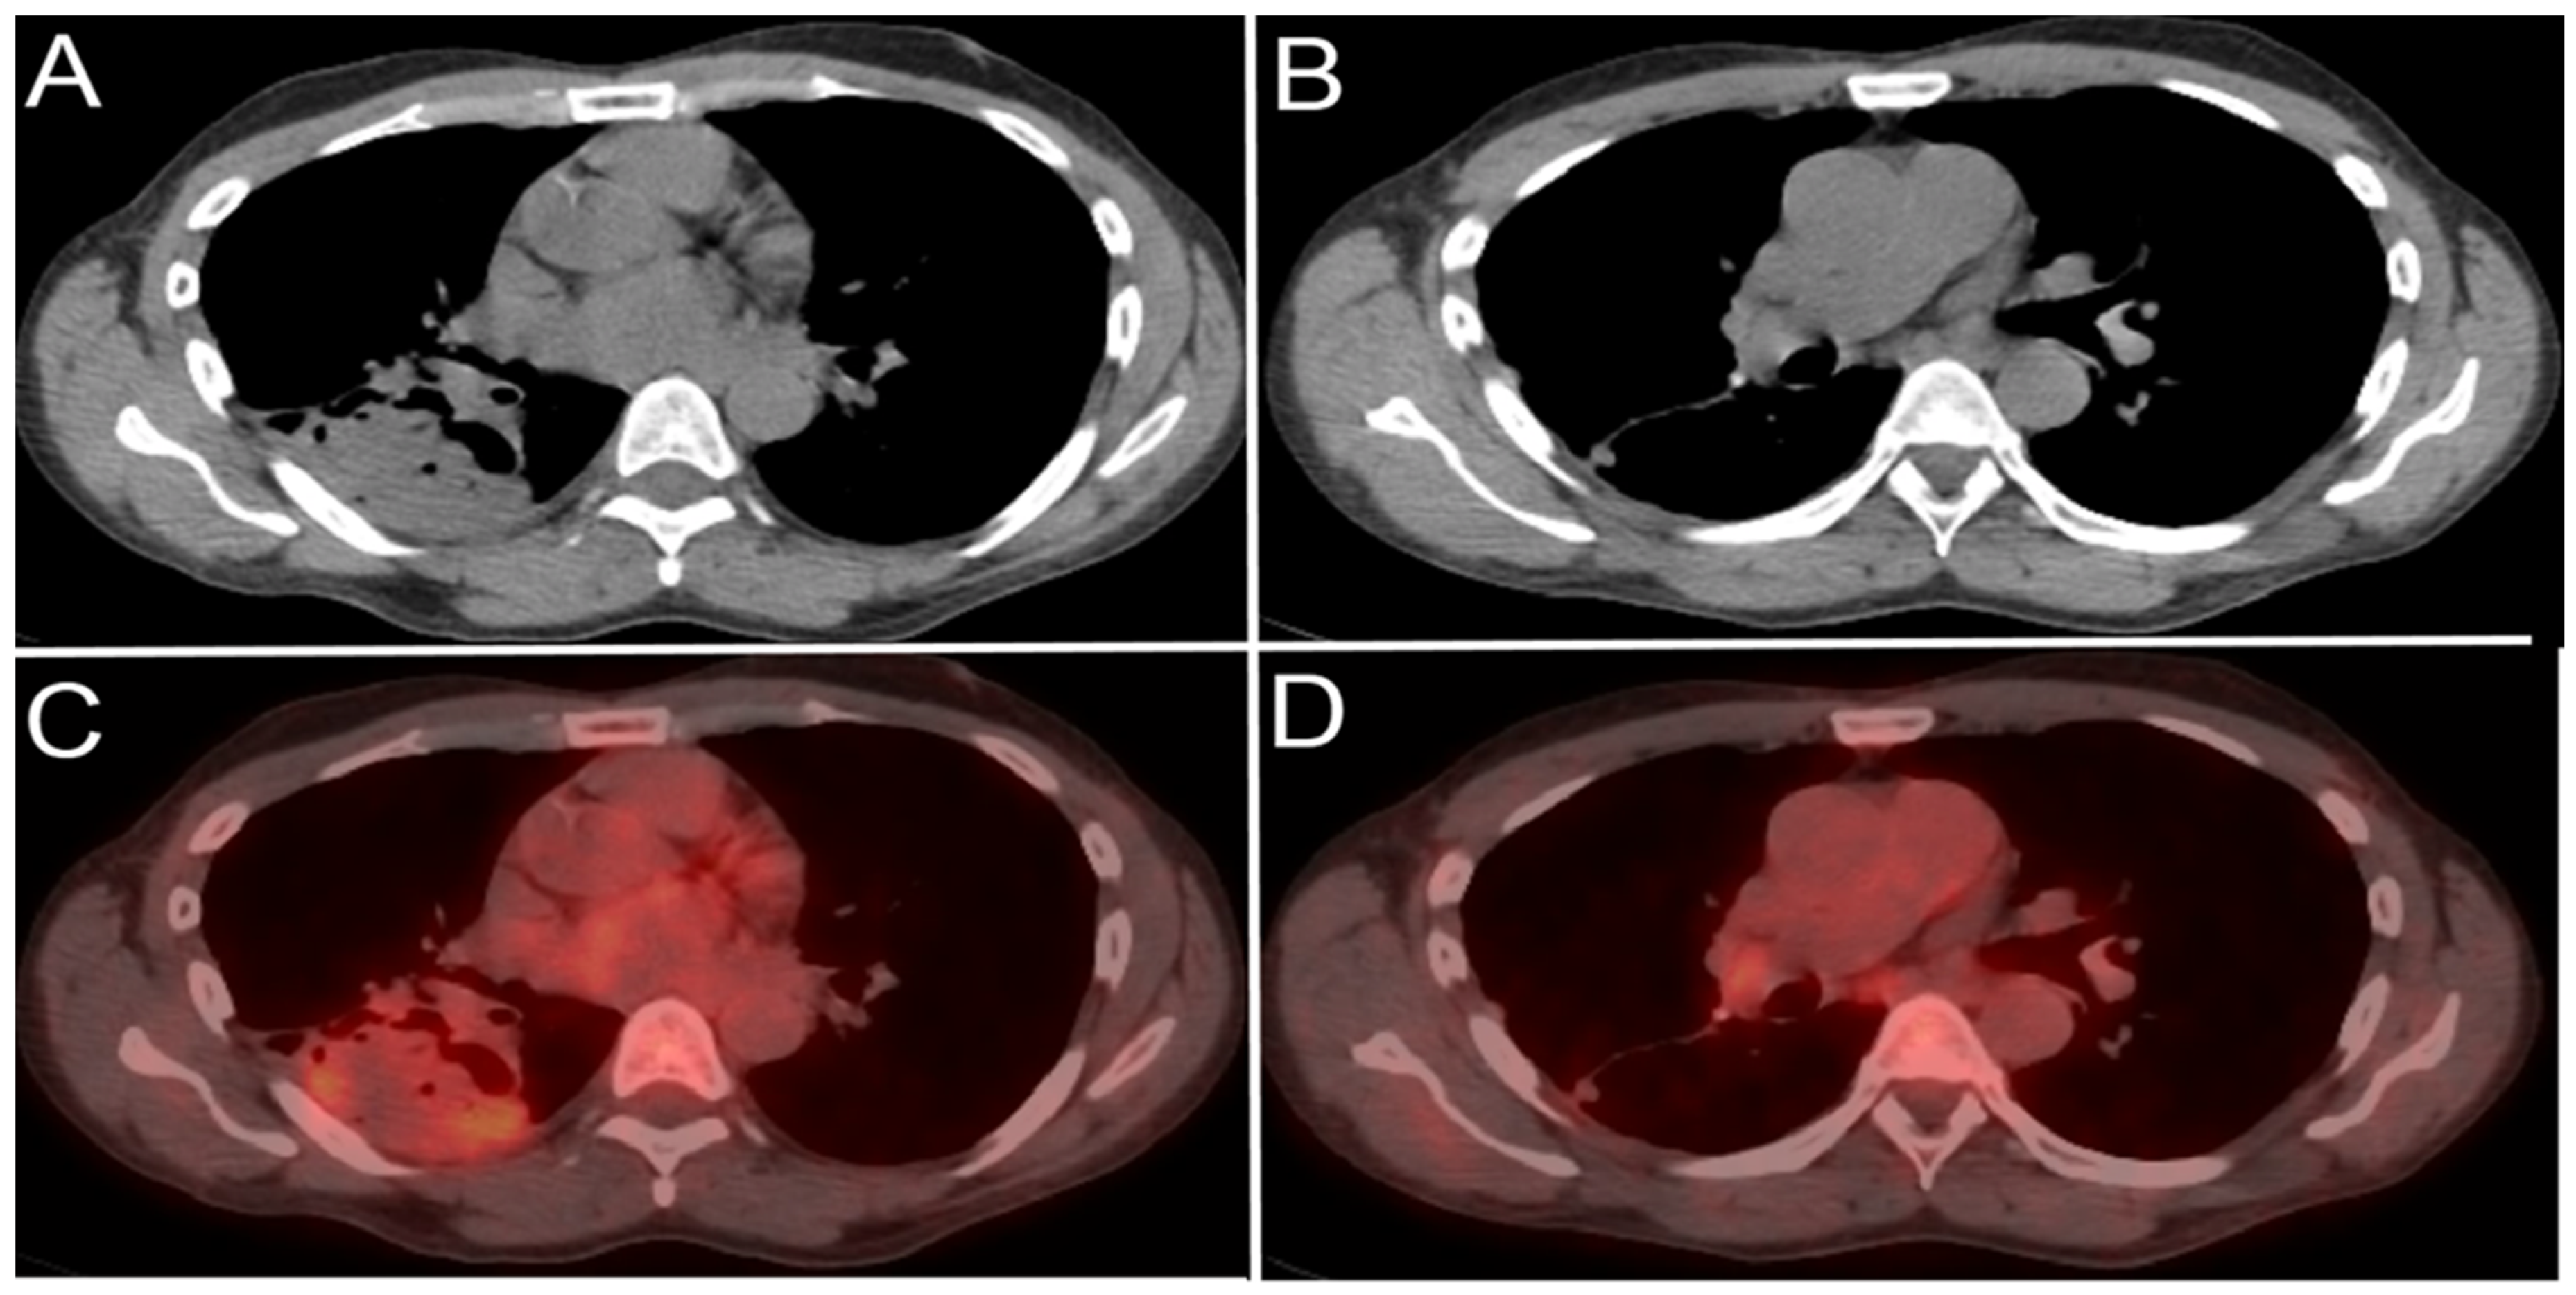

Facilitate learning with our scientific Pet/ct Lymphatic System gallery of hundreds of educational images. accurately representing photography, images, and pictures. perfect for research publications and studies. Browse our premium Pet/ct Lymphatic System gallery featuring professionally curated photographs. Suitable for various applications including web design, social media, personal projects, and digital content creation All Pet/ct Lymphatic System images are available in high resolution with professional-grade quality, optimized for both digital and print applications, and include comprehensive metadata for easy organization and usage. Explore the versatility of our Pet/ct Lymphatic System collection for various creative and professional projects. Multiple resolution options ensure optimal performance across different platforms and applications. Whether for commercial projects or personal use, our Pet/ct Lymphatic System collection delivers consistent excellence. Professional licensing options accommodate both commercial and educational usage requirements. Each image in our Pet/ct Lymphatic System gallery undergoes rigorous quality assessment before inclusion. Time-saving browsing features help users locate ideal Pet/ct Lymphatic System images quickly. Advanced search capabilities make finding the perfect Pet/ct Lymphatic System image effortless and efficient. Comprehensive tagging systems facilitate quick discovery of relevant Pet/ct Lymphatic System content. Instant download capabilities enable immediate access to chosen Pet/ct Lymphatic System images.